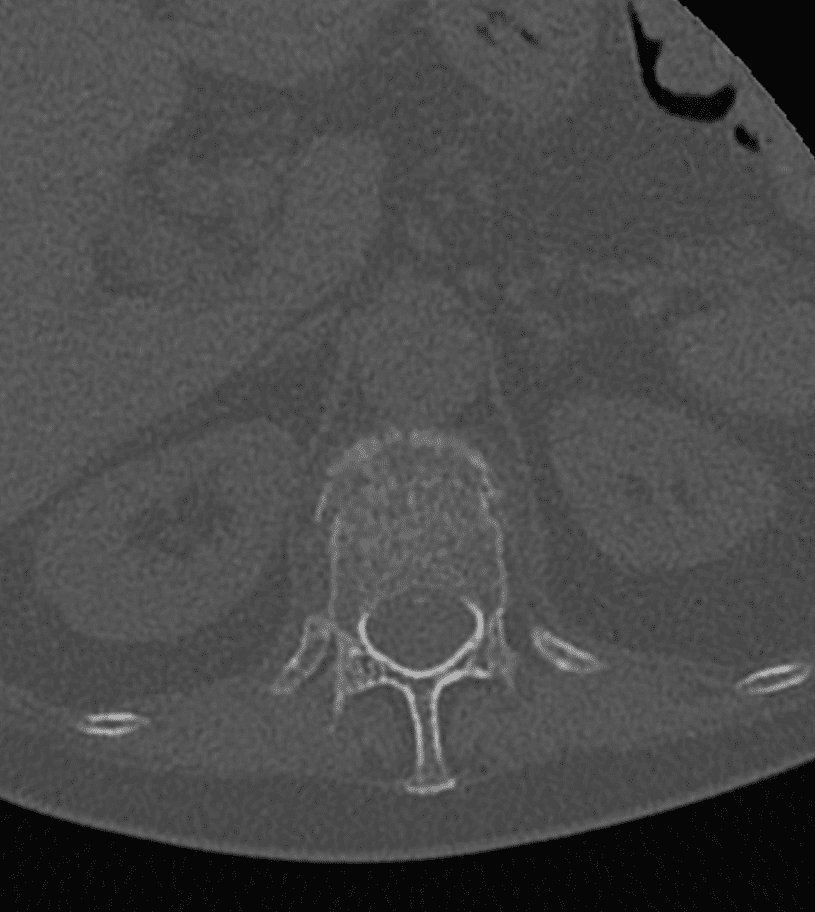

Guidage par imagerie

À l’aide de la fluoroscopie et/ou du scanner, l’équipe médicale guide avec précision une aiguille jusqu’au site de la fracture, en s’assurant d’éviter les structures sensibles.

Insertion et déploiement de l’implant

L’implant SPINEJACK est introduit dans le corps vertébral. Une fois en place, il est progressivement déployé pour redresser la vertèbre et restaurer sa hauteur, améliorant ainsi la posture et réduisant la douleur.